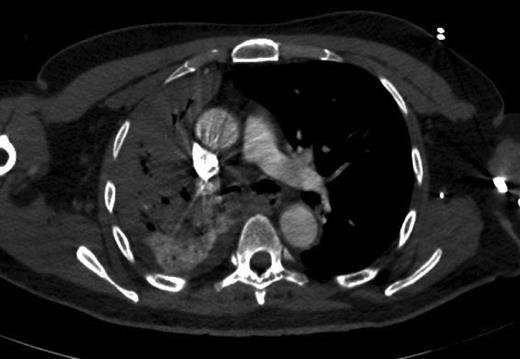

Since his history and clinical findings were very suspicious of TB, he was reviewed by the respiratory team. Empirical anti-tubercular therapy was suggested after sputum cultures were sent for acid fast bacilli (AFB) and a CT thorax showed a right upper lobe collapse and a 3-cm apicoposterior cavity. There was also consolidation seen in the right middle and lower zone as well as the left lung (Fig. 1). Also noted was right-sided neck lymphadenopathy (largest 17 mm). All these findings were consistent with pulmonary TB.

CT thorax—right-sided upper and mid zone collapse + consolidation.